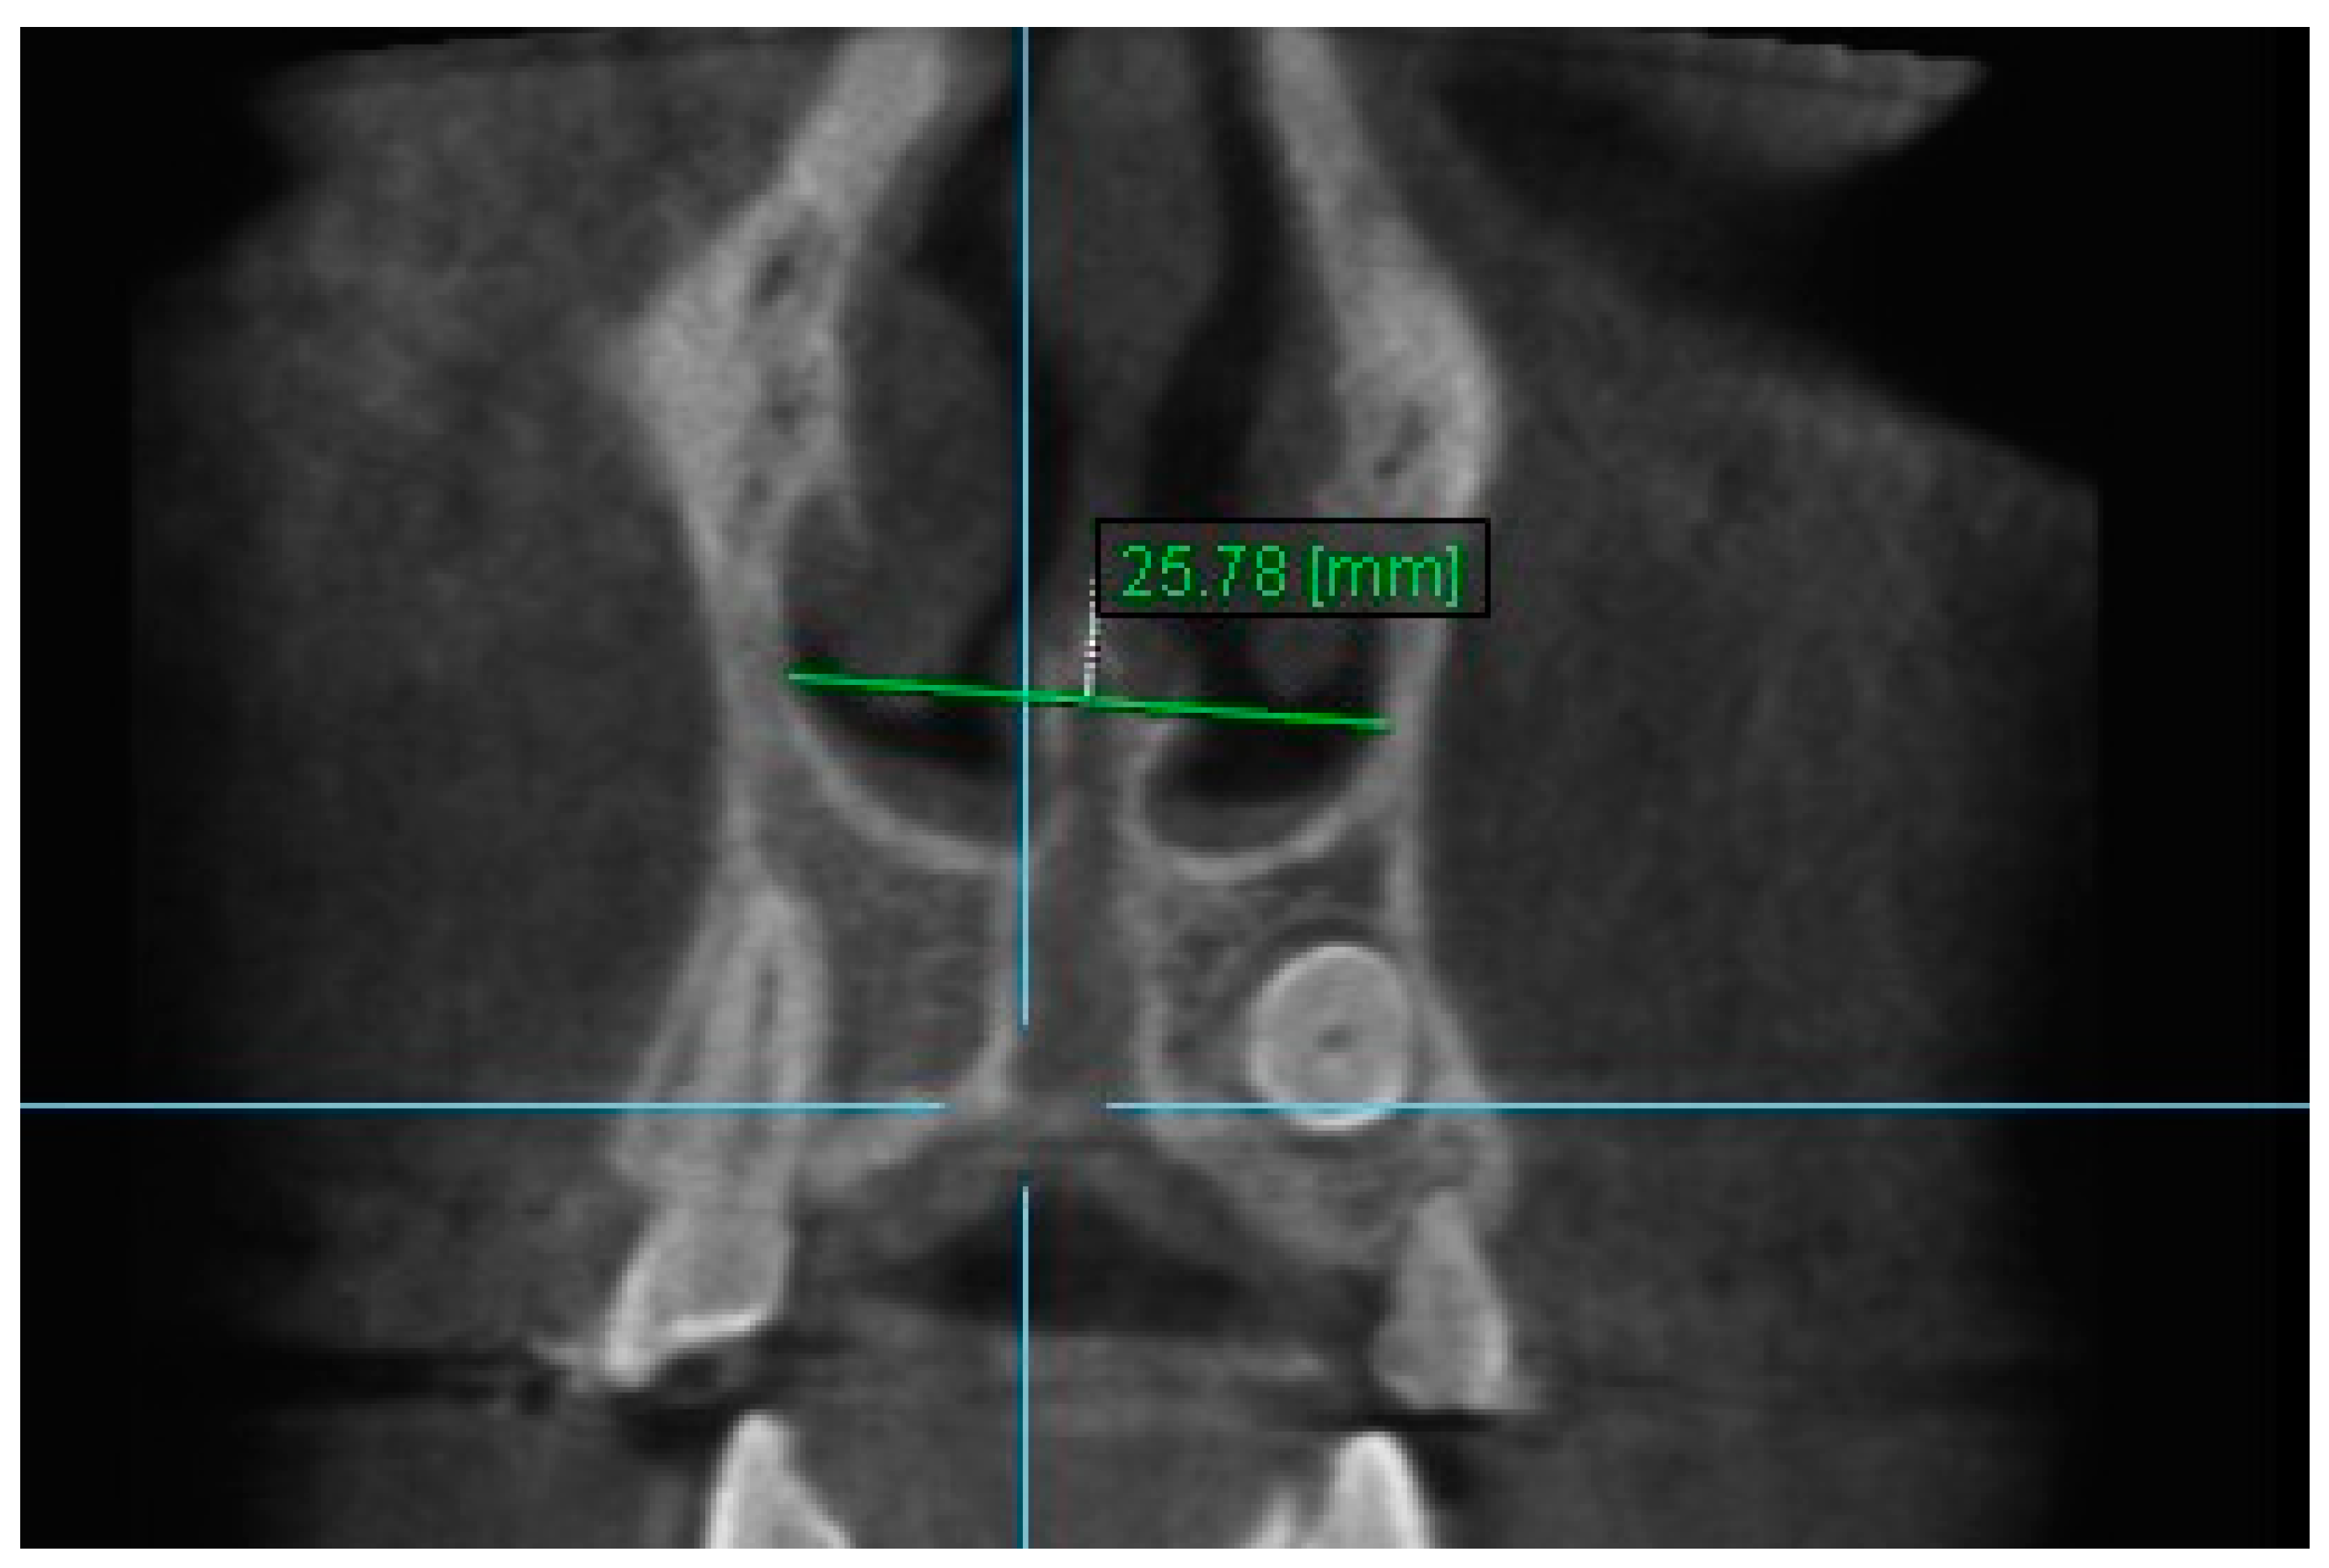

4. Nasal Width 4: The maximum distance between the inner right surface of nasal cavity and nasal septum on coronal slice through the center of mesial buccal root of the first premolar (Figure 6).

Figure 6.

Nasal Width 4.